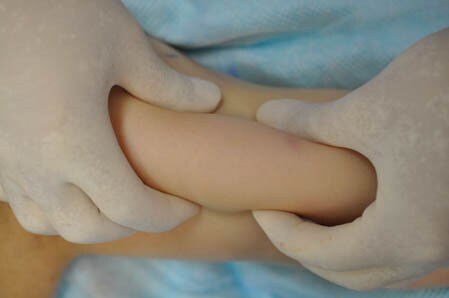

上の画像の部分をつまんでみましょう。

↓ ↓ ↓